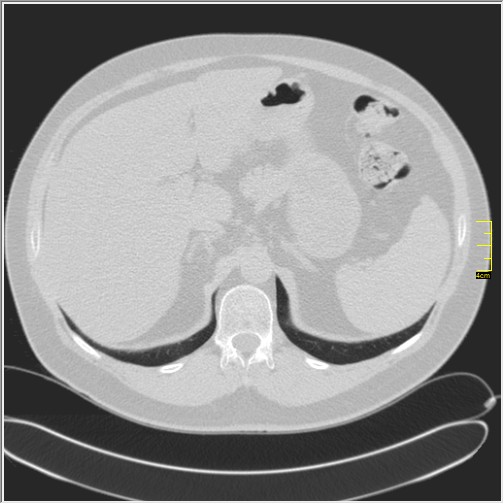

Četiri dana kasnije. Isti pacijent dolazi sa istim pulmologom. Situacija je sada sasvim drugačija. Temperatura 39.5 C. Saturacija 92. Laboratorija daleko gora. Uradim CT pluća. Ovo je izašlo.

Severity score 15/25. Pacijent je upućen na bolničko lečenje.

Ono što zbunjuje, a to se ponavlja zadnjih 10 dana, je da fibroza nastupa u progresivnoj fazi, znači na početku bolesti. Toga nije bilo do sada. Sledećih dana ću o tome.

Ovo je samo 4 dana. Od zdravlja do teške bolesti. Pacijent je 45 godina starosti, očigledno nije povećane težine, kaže za sebe da je bio sportista. U anamnezi nije naveo nikakve bitne bolesti.